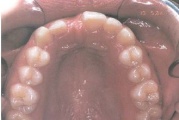

Vali sind huvitav pilt ja me näitame sellega seotud haigust ja sümptomeid